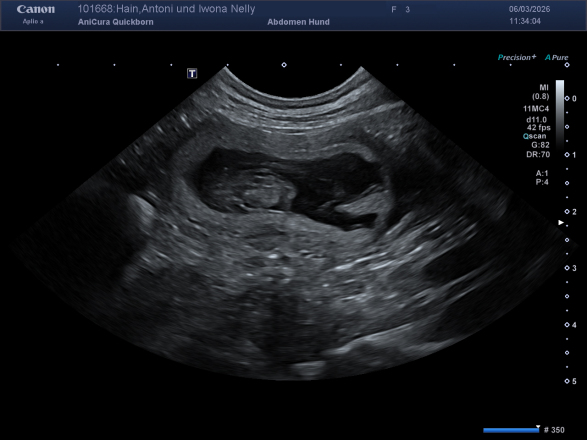

Am 4. April hat unsere Nelly ihren zweiten Wurf zur Welt gebracht –

Es sind wieder 9 gesunde, wundervolle Welpen ✨